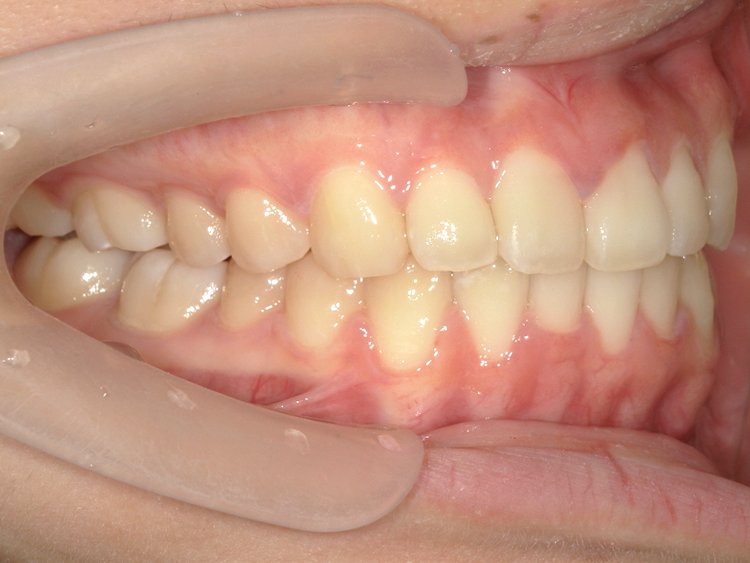

症例4

Before

After

| 主訴 | 上下前歯のがたつき |

| 年齢 | --- |

| 治療 期間 |

約9ヶ月 |

| 治療 内容 |

インビザラインiGoで上下顎の治療。 |

| 治療費 | ¥550,000(税込)/調整料含む |

| 治療のリスク | 矯正終了後は、リテーナーを指示通りに使用し、歯の後戻りを防ぐ必要があります。 |